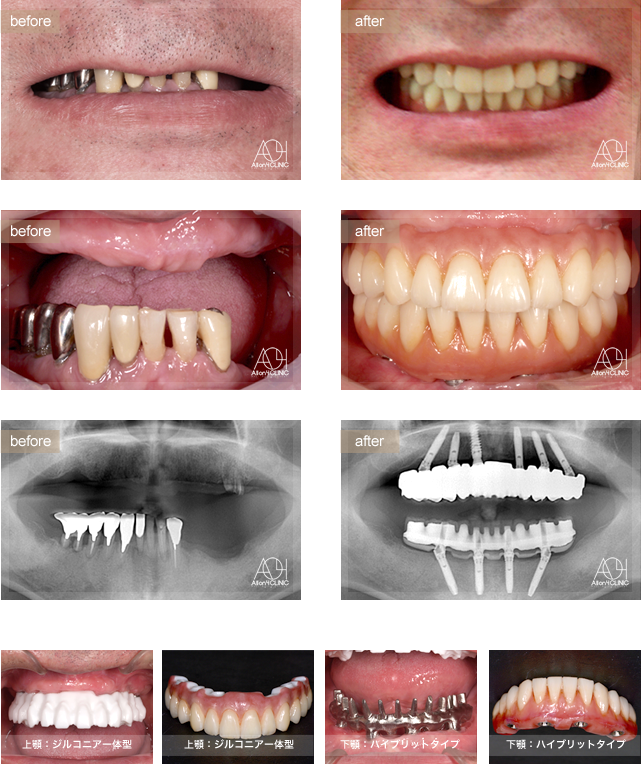

- Maxilla All-on-4

- Under All-on-4

上顎は6本のインプラントを埋入。下顎はAll-on-4。

上顎上部構造はジルコニア一体型。(歯肉:セラミック歯:セラミック)を採用。

下顎はハイブリッドタイプ(歯肉:ハイブリッド基底面のみセラミック処理歯:ハイブリッド)